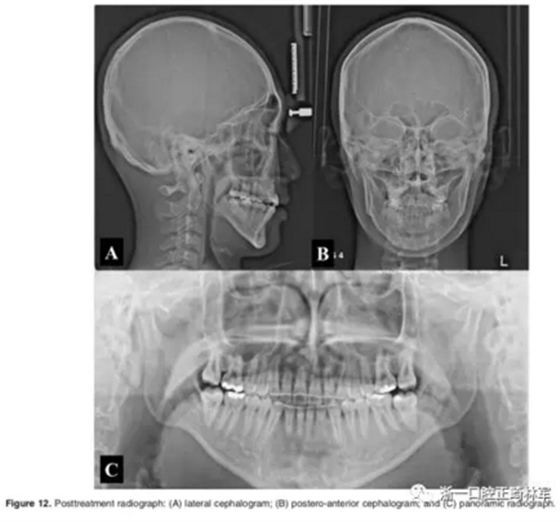

影像學:頭顱側位片示:矢狀向和垂直向骨骼發(fā)生變化(ANB角,3°;SN-MP,51°);上頜切牙略前傾(U1-SN,106°),與下頜切牙一致(IMPA,75°);病人的面部輪廓得以保持。全景片示:由于牙齒萌出,上前牙區(qū)垂直向牙槽骨水平增加;雖然前牙牙根較彎曲,但其平行度仍可,且無明顯的牙根吸收。CBCT示:前牙唇側骨質連續(xù)性改善,牙根唇側支持組織變好,牙槽骨高度、厚度均有增加,但轉矩的改變一定程度上導致了局部應力的增大。